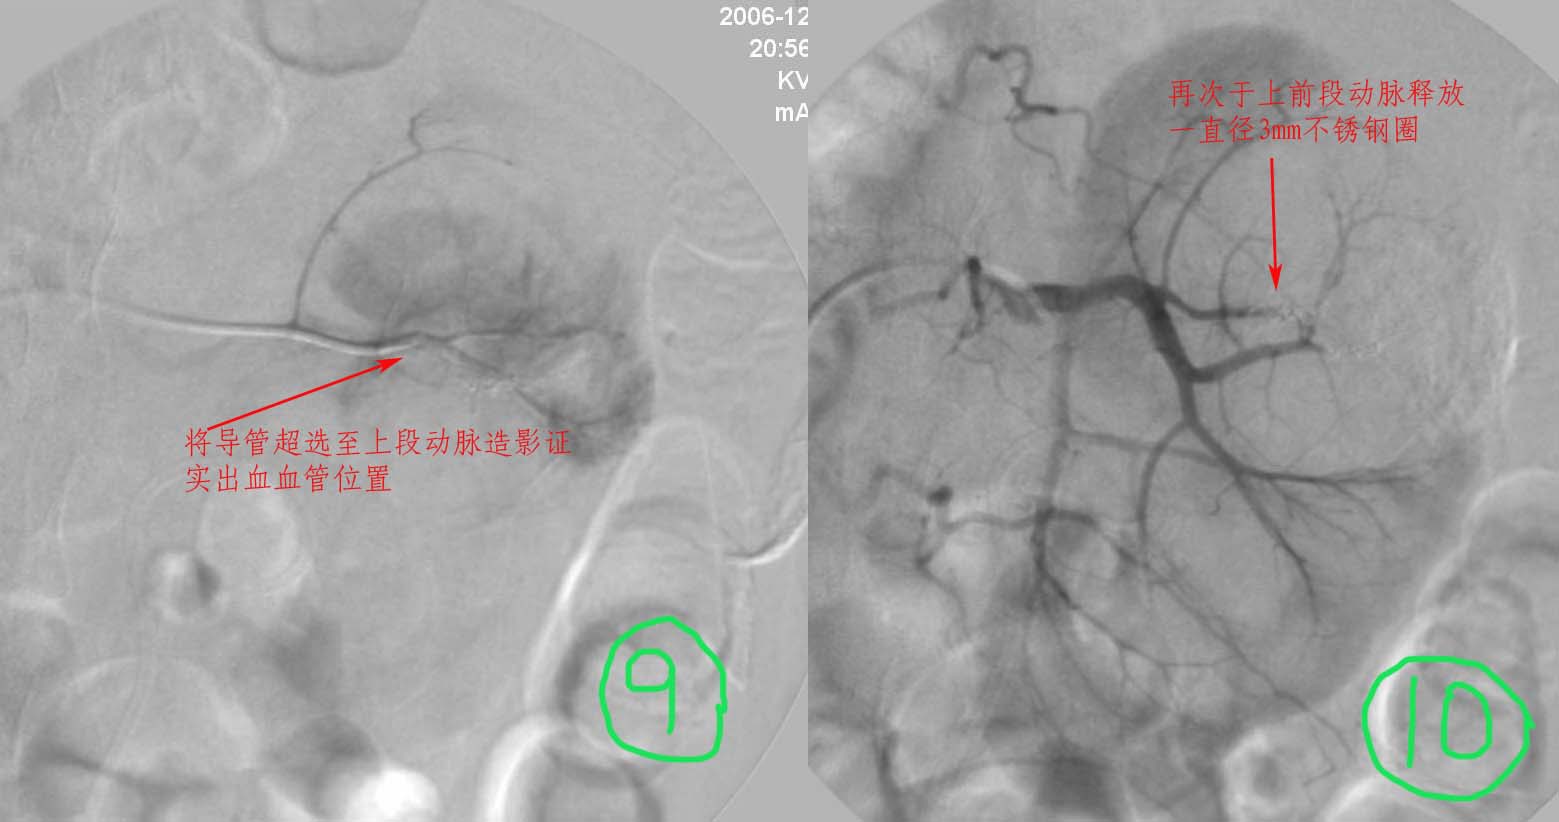

男性,45岁,因左输尿管与肾盂结合部结石住院治疗,经皮肾镜治疗失败后,改做开放手术.手术后3天出现血尿,5天保守治疗仍不能止血,申请肾动脉dsa,见下图片,发帖目的在于请各位分析判断出血部位.

介入治疗过程:

注:图5\6文字标示应为".....再次证实出血部位"